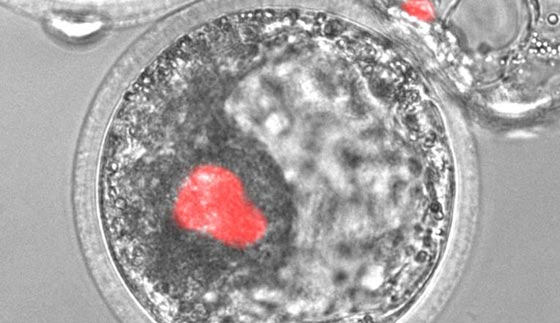

تظهر هذه الصورة المجهرية خلايا جذعية محفزة من صنع الإنسان، باللون الأحمر، مدموجة داخل جنين خنزير. ويأمل العلماء أن هذه الخلايا البشرية يمكن تسخيرها لصنع أعضاء لمرضى العمليات الزراعية يوماً ما

ويحاول الباحثون في جامعة كاليفورنيا وديفيس وغيرها من المؤسسات، بمعالجة هذه المشكلة من خلال زراعة الأعضاء البشرية داخل حيوانات، مثل الخنازير والأبقار. ويعرف خليط الحمض النووي البشري والحيواني هذا، باسم الكمير أو الكيميرا، وهو مصطلح مشتق من كلمة قديمة أطلقت على المخلوقات الهجينة الوحشية في الأساطير اليونانية.